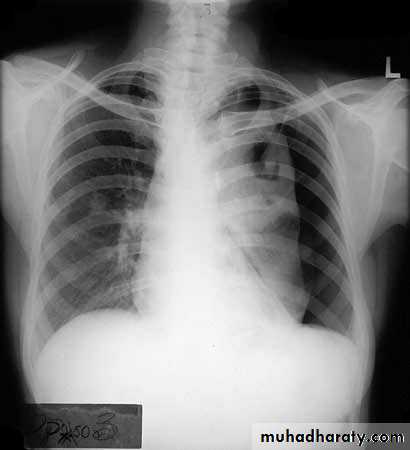

Differentiating the Causes of an Opacified Hemithorax

Atelectasis of an entire lungA large pleural effusion

Pneumonia of an entire lung

And a fourth cause: Post-pneumonectomy – removal of an entire lung

Atelectasis of the Lung

There is a shift of heart and hemidiaphragm toward side of opacification (toward side of volume loss)Pleural Effusion

It acts like a massPushing the heart and trachea away from the side of opacification

pneumonia

The hemithorax is opaque and there isno shift of the heart or tracheaThere may be an air bronchogram sign present

postpnemonectomy

The hemithorax eventually fibroses and becomes opaqueClues: There is frequently a resected fifth rib and/or surgical clips

quiz

Pleural effusion